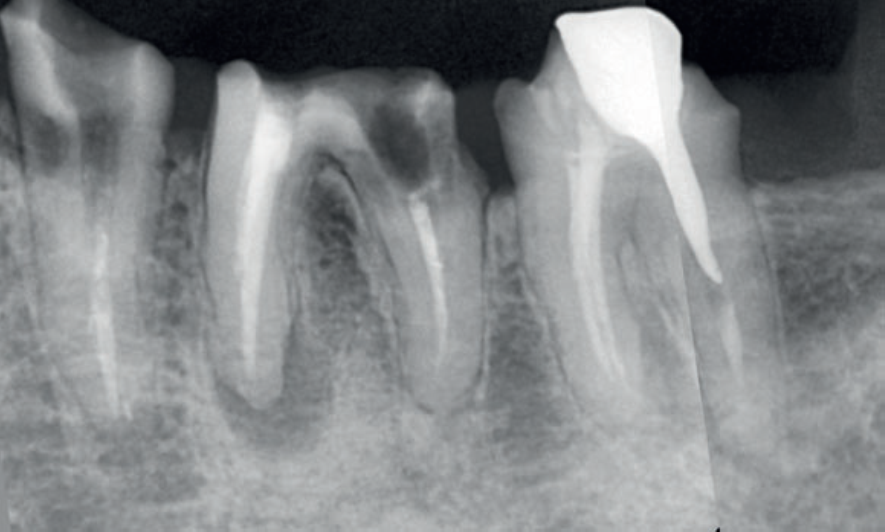

Ao serem instalados, os implantes que atingem um torque de inserção ≥ 32 Ncm podem ser imediatamente carregados com coroas unitárias de transição não oclusivas. Abaixo deste torque, ou em situações onde não desejamos correr riscos, em vez de uma coroa de transição, instala-se um cicatrizador personalizado contendo um perfil transmucoso com as mesmas características que a coroa provisória teria. Os objetivos dos cicatrizadores customizados nos casos de instalação do implante imediatamente após a exodontia são: selar o sítio cirúrgico respeitando o perfil do alvéolo de extração, estabilizar o coágulo sanguíneo e favorecer a regeneração óssea com o material substituto, evitar o colapso de tecidos moles durante o período de cicatrização e desenvolver um perfil de emergência protético ideal para a futura coroa sobre implante, baseado na anatomia do dente natural extraído, sem receber carga oclusiva.

Nos casos de instalação de implantes em regiões edêntulas, também é possível empregar cicatrizadores personalizados, desenvolvendo um perfil de emergência protético ideal para a futura coroa sobre implante, baseado na anatomia do dente natural ausente. Os dois procedimentos restabelecerão o perfil de emergência original do paciente durante a fase de cicatrização/osseointegração dos implantes, devolvendo a harmonia dentogengival, com a recuperação das papilas interdentais e a reconstituição do arco gengival côncavo, com altura adequada da margem em relação aos dentes adjacentes.